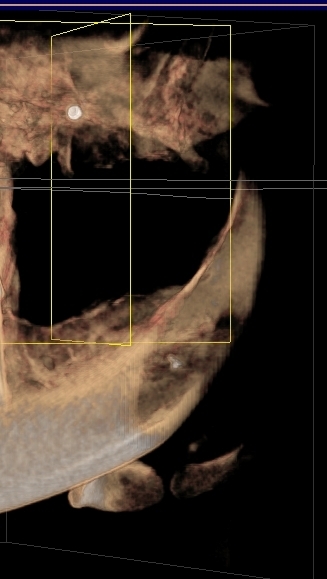

Может ли быть, что через пять лет мне аукнулся неудалённый материал, и боли будут только усугубляться? Прилагаю скриншот КТ

Теоретически ваши симптомы могут быть связаны с инородным материалом в надкостнице, но я не думаю, что причина ваших беспокойств связана именно с этим материалом. Необходимо хорошенько изучить область беспокойства.